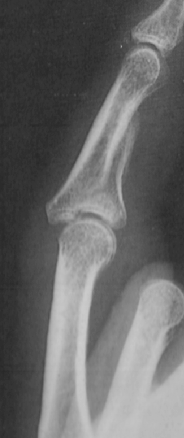

| Hätten Sie es erkannt? | |